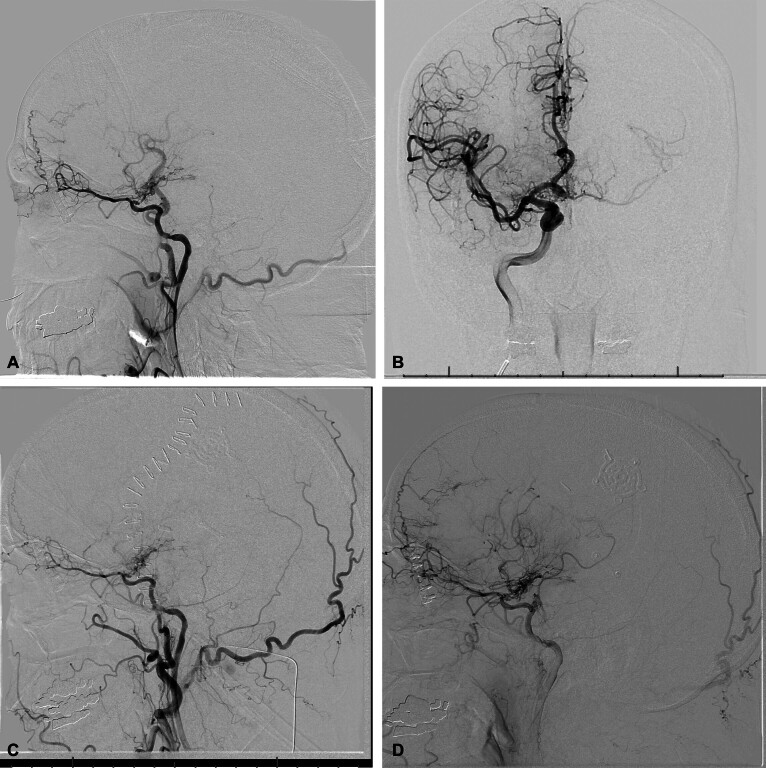

一位70岁的男性,由于左颈内动脉(ICA)闭塞而发生短暂性脑缺血发作(tia),他接受了颈外动脉到ICA的搭桥手术,该搭桥术后闭塞。在左心室流出道梗阻的情况下,经胸连续超声心动图优化后,患者出现失语,并以诱发高血压解决。

A 70-year-old man with transient ischemic attacks (TIAs) due to left internal carotid artery (ICA) occlusion underwent external carotid to ICA bypass which occluded postoperatively. He developed aphasia which resolved with induced hypertension optimized by using serial transthoracic echocardiography in the setting of left ventricle outflow tract obstruction.